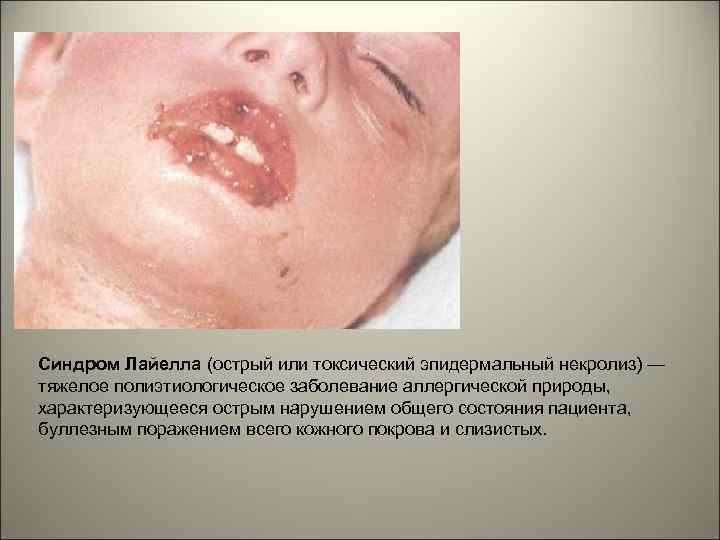

• У ВИЧ-инфицированных больных часто возникают медикаментозные (ятрогенные) поражения десен, пародонта, слизистой оболочки рта (медикаментозный стоматит с изъязвлениями, полиморфная экссудативная эритема, синдром Стивенса. Джонсона, синдром Лайелла, лихеноидные реакции, пигментации и т. ).

Синдром Лайелла (острый или токсический эпидермальный некролиз) — тяжелое полиэтиологическое заболевание аллергической природы, характеризующееся острым нарушением общего состояния пациента, буллезным поражением всего кожного покрова и слизистых.